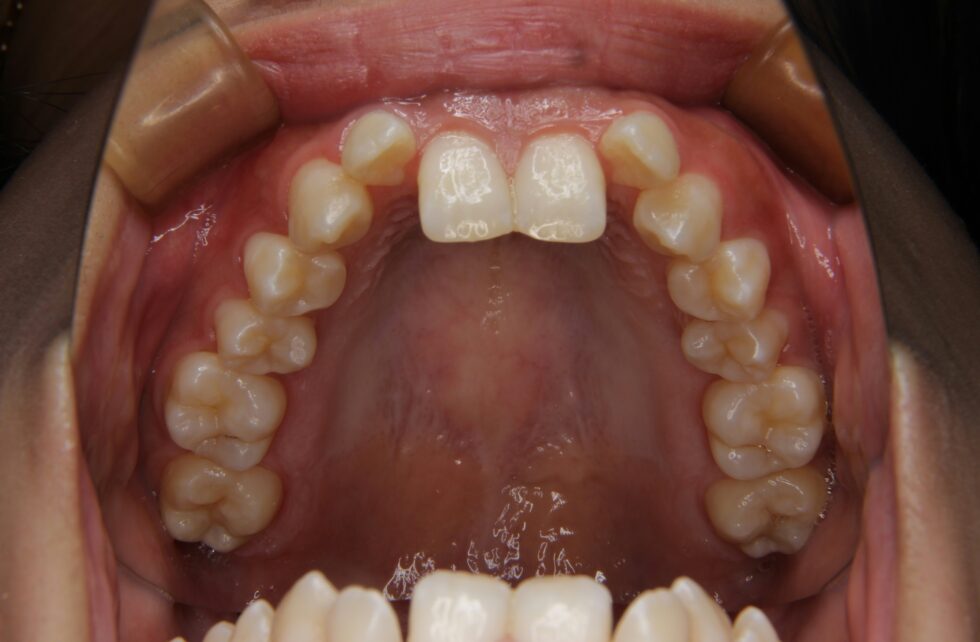

初診時年齢24歳の女性 上顎前歯の内傾を主訴にご来院いただいた。長年、前歯が内側を向いていることを気にされていたが治療を行う勇気が出なかったとのことであった。しかし、咬合時に上顎前歯に痛みを感じるようになったことから治療を希望された。セファログラム他の分析から咬合力の極めて強いと考えられる骨格をされていることが分かった。上あごの前歯が内側を向いた骨格性上顎前突で、アングルの分類Ⅱ級2類と診断した。咬合力が強いと歯の動きは緩徐で、前歯のかみ合わせが深くなり、上あごの前歯の後退が困難になる場合がある。このため、上顎左右側小臼歯を抜歯していただき、矯正用アンカープレートを併用して、上下顎マルチブラケット装置を使用して動的治療を行った。内側を向いていた上顎前歯は適正な角度とすることができた。